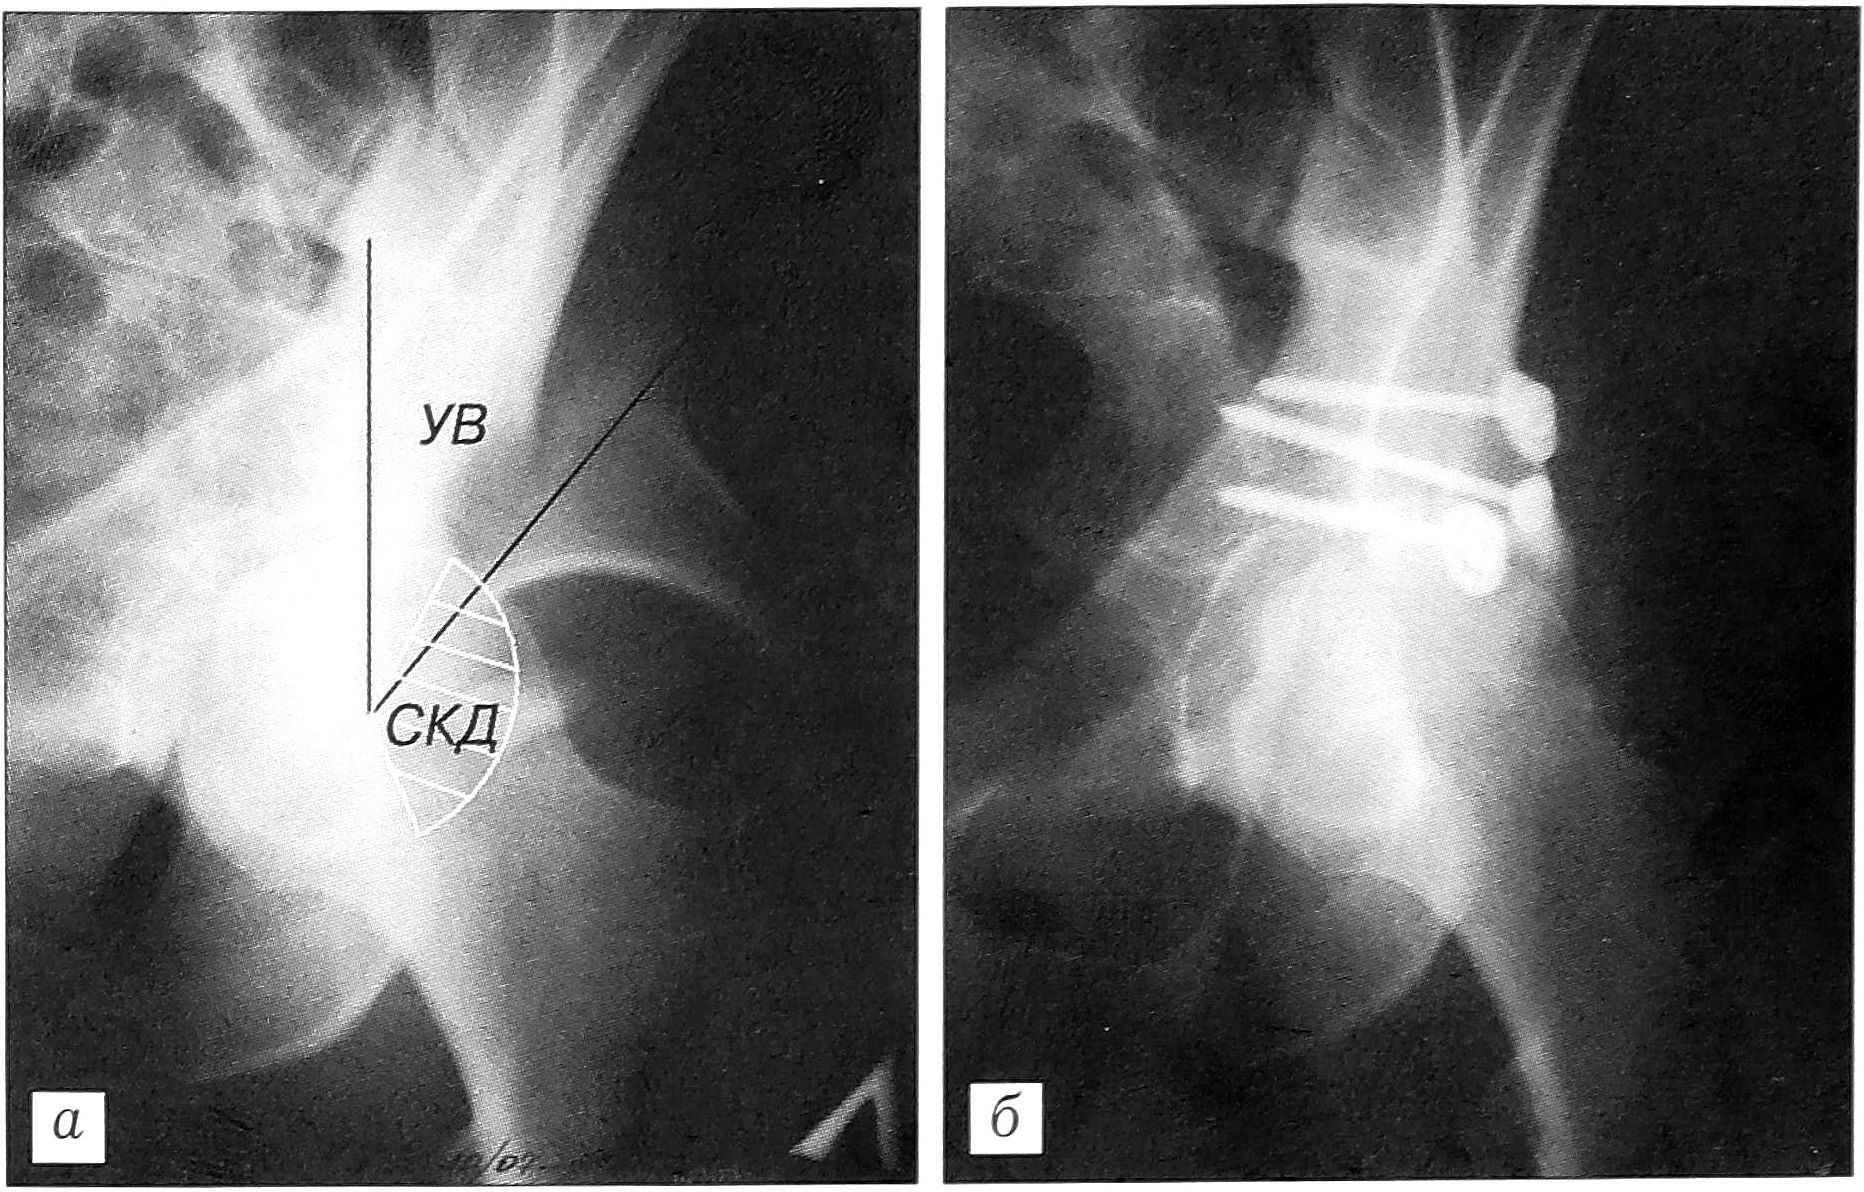

При госпитализации для уточнения диагноза всем больным независимо от тяжести состояния проводили рентгенографию тазобедренного сустава в трех проекциях. Основная информация о величине и расположении дефекта заднего края вертлужной впадины может быть получена при внутренней косой рентгенографии [3, 9]. Нами в эксперименте на костных препаратах таза был определен угол Виберга, который на рентгенограмме при внутренней ротации таза в 30° проекционно увеличивается на 10% и составляет в среднем 40±2,3°. Если дефект заднего края находился в секторе этого угла, перелом расценивали как задневерхний, если частично проходил через него — как задний, если не проходил — как задненижний. Для измерения протяженности контура дефекта суставной поверхности в качестве количественного показателя использовали не длину дуги дефекта, а ее центральный угол. Наибольшую величину он имел при задневерхних переломах, т.е. когда дефект располагался в нагружаемом секторе впадины. Помимо протяженности дефекта, имеет значение его глубина (см. рисунок).

Рентгенограммы тазобедренного сустава (наружная косая проекция с ротацией таза 30°) больного с краевым переломом вертлужной впадины (УВ — угол Виберга, СКД — сектор краевого дефекта). а — при поступлении; б — после операции.

Абсолютными показаниями к остеосинтезу считали переломы со смещением отломка более чем на 2 мм [8], с глубиной краевого дефекта более четверти радиуса впадины, если он располагался в заднем или задневерхнем секторе, а протяженность контура дефекта (величина центрального угла его дуги) была не менее 10°. Показанием к операции служили также невправимые вывихи, при которых, независимо от величины дефекта края, была необходима ревизия сустава с целью удаления интерпонированных тканей. Такая ситуация имела место в 8 случаях. Для уточнения диагноза у 6 пациентов применялась компьютерная томография.